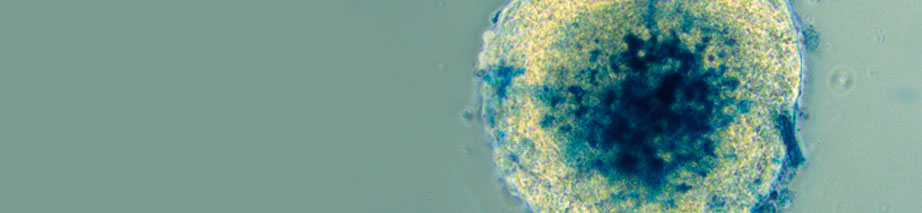

Compartilhar: Chamada Participe Link do banner Palestra apresenta método alternativo ao uso de animais no desenvolvimento de f…